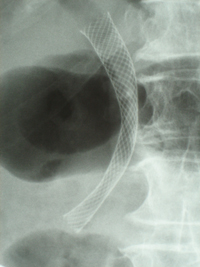

Prothèse du colon